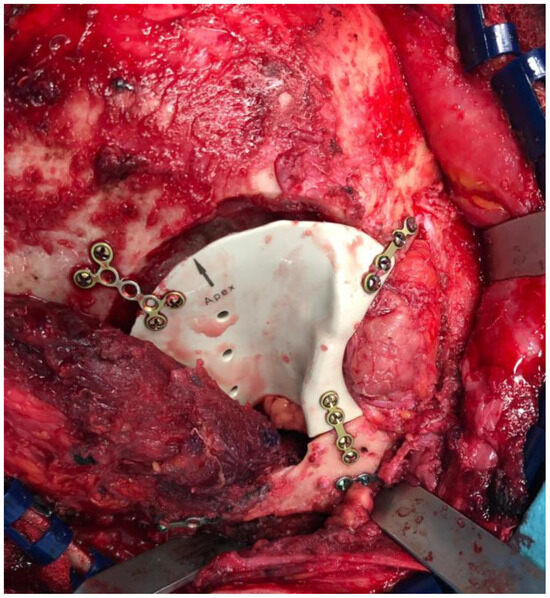

2.3. Surgical Procedure

4.3. Reconstruction with Patient-Customized Implants (PSIs)

4.4. Intraoperative Imaging